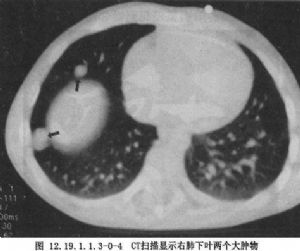

Ⅳ期:肿瘤有血源性转移,如肝、肺、骨、脑等(图12.19.1.1.3-0-4)。